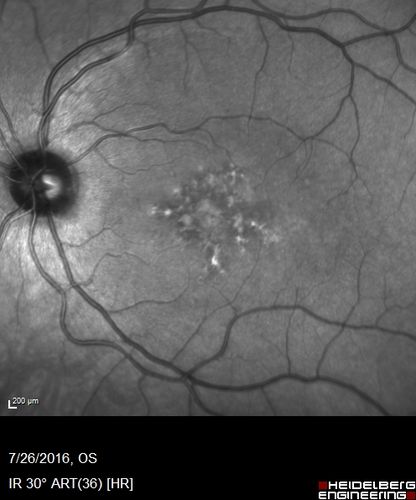

Pattern Dystrophy - Probably Early Butterfly

33 year old with normal vision and no visual complaints - normal color vision